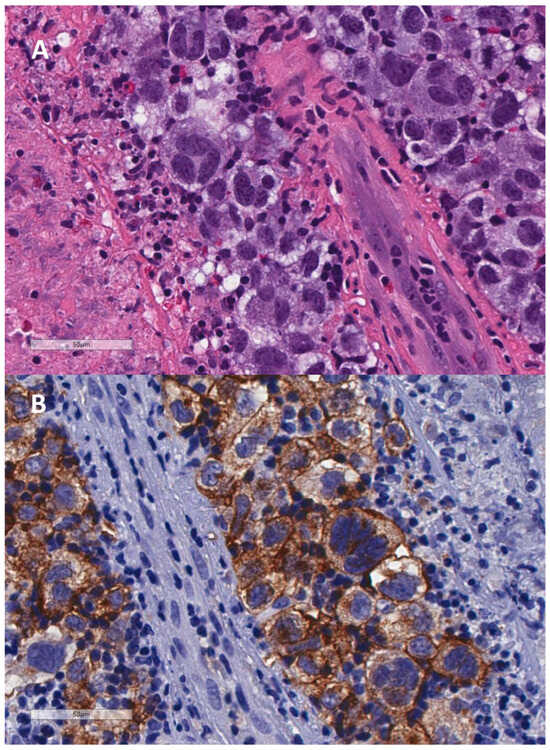

- Lajoie, V.; Lemieux, B.; Sawan, B.; Lichtensztejn, D.; Lichtensztejn, Z.; Wellinger, R.; Mai, S.; Knecht, H. LMP1 mediates multinuclearity through downregulation of shelterin proteins and formation of telomeric aggregates. Blood 2015, 125, 2101–2110. [Google Scholar] [CrossRef] [PubMed] [PubMed Central]

- Knecht, H.; Johnson, N.A.; Haliotis, T.; Lichtensztejn, D.; Mai, S. Disruption of direct 3D telomere-TRF2 interaction through two molecularly disparate mechanisms is a hallmark of primary Hodgkin and Reed-Sternberg cells. Lab. Investig. 2017, 97, 772–781. [Google Scholar] [CrossRef]

- Contu, F.; Rangel-Pozzo, A.; Trokajlo, P.; Wark, L.; Klewes, L.; Johnson, N.A.; Petrogiannis-Haliotis, T.; Gartner, J.G.; Garini, Y.; Vanni, R.; et al. Distinct 3D Structural Patterns of Lamin A/C Expression in Hodgkin and Reed-Sternberg Cells. Cancers 2018, 10, 286. [Google Scholar] [CrossRef]